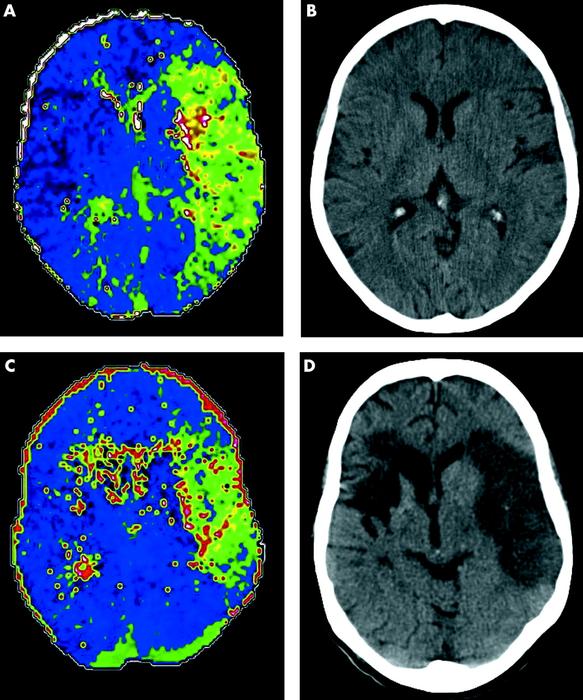

[Figure caption and citation for the preceding image starts]: (A) Perfusion CT (time to peak (TTP) map) of acute left MCA ischaemia sub-three hours and (B) equivalent non-contrast CT. Perfusion CT predicts final infarct volume in the absence of arterial recanalisation: (C) three hour TTP map and (D) 24 hour non-contrast CTMuir KW et al. Neuro 2005; 76: iii19-iii28; used with permission [Citation ends].